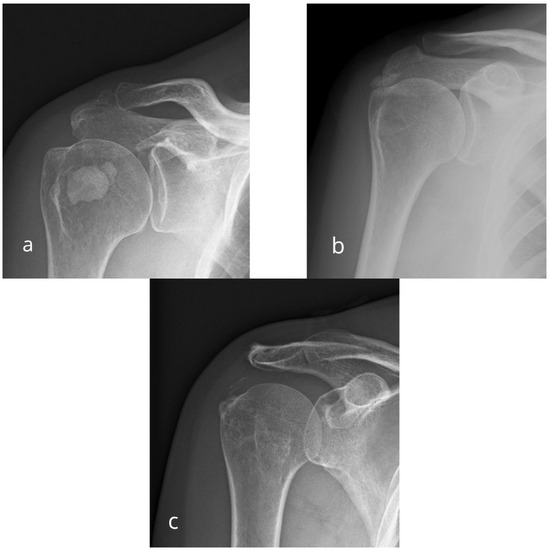

Association Between Osseous Shoulder Morphology and Pathoanatomical Characteristics of Calcific Deposits in Rotator Cuff Calcific Tendinitis

by Andro Matković, Mia Grgić, Ines Trkulja, Marija Ivković, Thomas Ferenc, Nikolina Jurjević, Božidar Šebečić and Vinko Vidjak

Diagnostics 2025, 15(22), 2908; https://doi.org/10.3390/diagnostics15222908 - 17 Nov 2025

Viewed by 625

Abstract

Background/Objectives: Rotator cuff calcific tendinitis (RCCT) is a common cause of shoulder pain. The role of acromial morphology in RCCT pathogenesis remains unclear. This study aimed to evaluate association between acromial morphological parameters and calcific deposit characteristics in patients with RCCT. Methods: We [...] Read more.